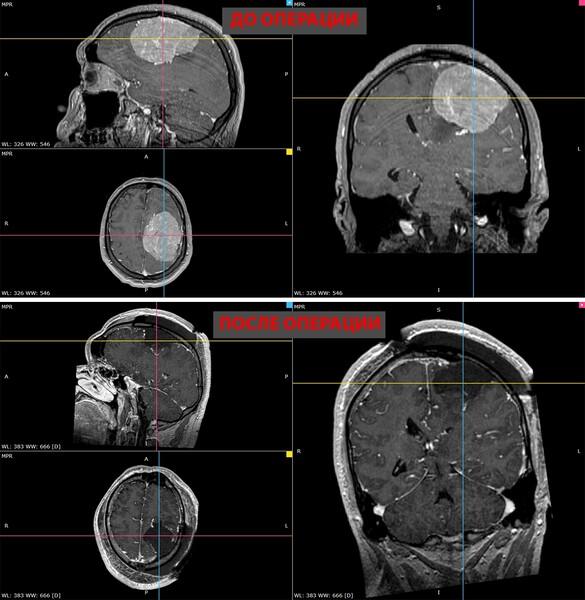

Врачи из Новосибирска спасли пациента с гигантской опухолью мозга

Фото: Сиб.фм / НМИЦ им. ак. Е.Н. Мешалкина Минздрава России

В Новосибирске врачи провели сложную операцию 35-летнему пациенту и удалили гигантскую опухоль головного мозга. Об этом сообщили в НМИЦ имени Мешалкина Минздрава России.

Проблемы у мужчины начались в ноябре прошлого года. Появилась слабость в правой руке и нарушения речи. Обследование показало наличие менингиомы более восьми сантиметров в левом полушарии мозга. Состояние постепенно ухудшалось, и к концу года двигательные функции значительно снизились.

Операция длилась около пяти часов и завершилась успешно — опухоль удалили полностью. Восстановление пошло быстро: уже на следующий день появились движения в руке, а через две недели пациент смог снова самостоятельно ходить. Речь и двигательные функции восстановились, а приступы прекратились.